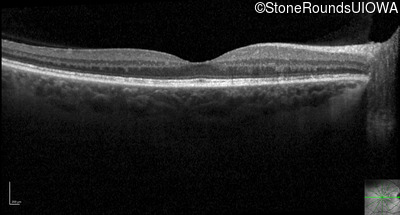

Optical Coherence Tomography - Right - 20/16 -1

Exemplar / OCT Stack

OCT Stack

Optical Coherence Tomography - Left - 20/16 -1